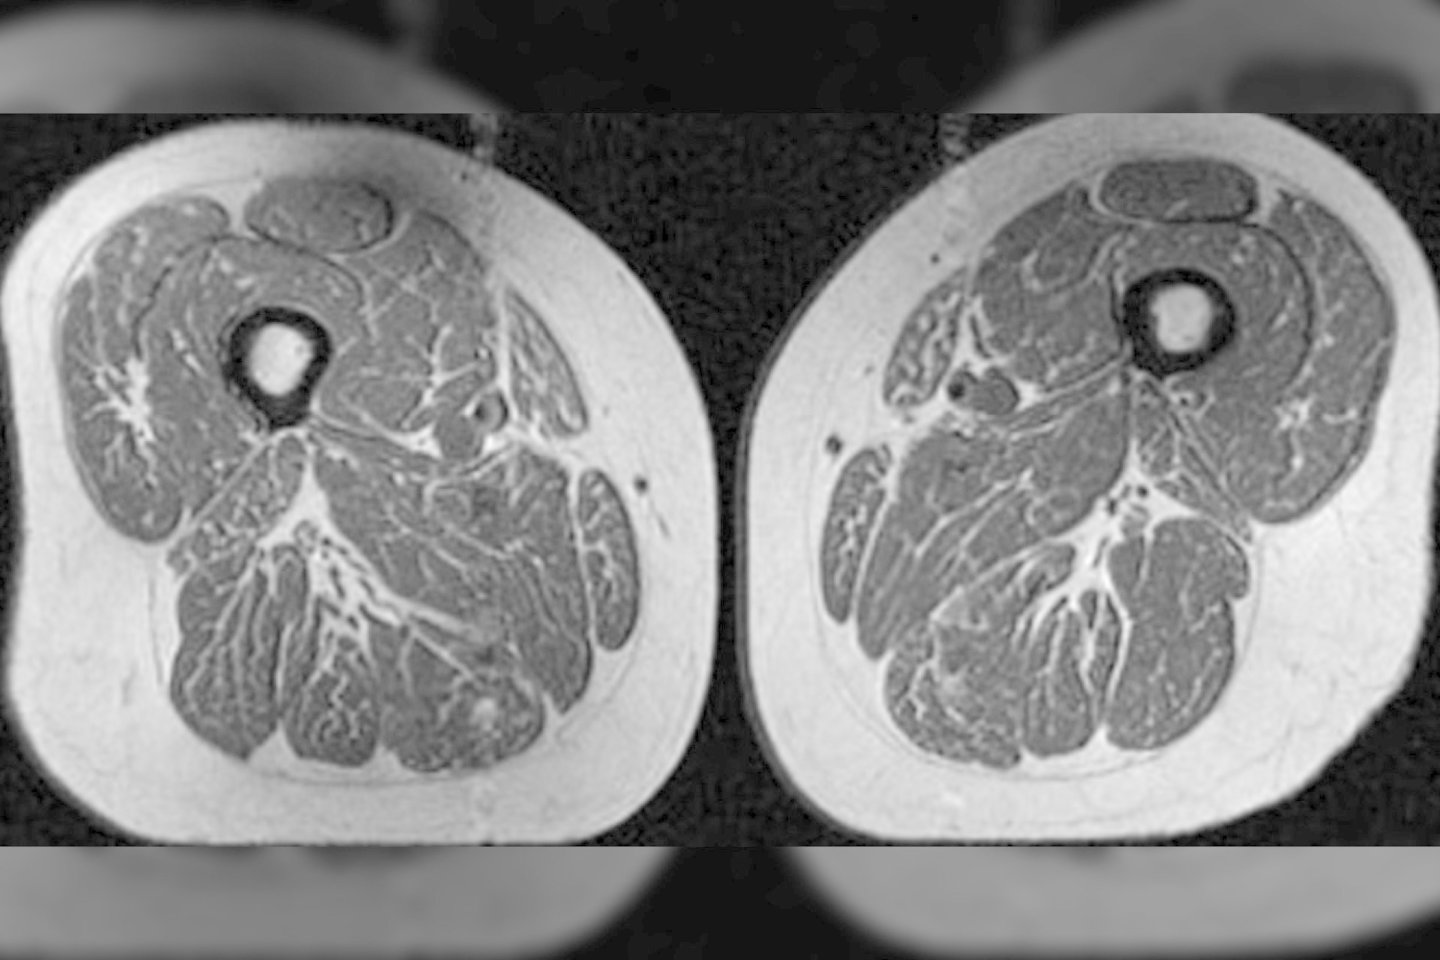

Paslėpti riebalų dryžiai tarp raumenų skaidulų ir jų viduje gali signalizuoti apie rimtas sveikatos problemas, pabrėžė Z. Akkaya. Ji yra naujo tyrimo, kuriame analizuojama, kaip itin perdirbtas maistas veikia raumenų riebalus žmonėms, kai jiems gresia kelio osteoporozė, pagrindinė autorė.

„Kyla nerimas, nes tyrimo dalyviams atlikti vaizdiniai tyrimai, kai jie neturėjo jokių kelio osteoartrito požymių, bet jau pasižymėjo sutrikusia raumenų kokybe“, – sakė Z. Akkaya.

Riebalų ląstelės silpnina raumenis, nes trukdo augimui ir neleidžia raumenų skaiduloms tinkamai regeneruotis. Silpni raumenys yra pagrindinė kelio osteoartrito, dažniausios sąnarių ligos, kuria serga beveik 375 milijonai žmonių visame pasaulyje, priežastis.

„Šlaunies raumenys yra labai svarbūs kelio sąnario stabilumui, o bet koks jų jėgos ar tonuso praradimas gali padidinti sąnariui tenkantį krūvį, ypač nutukusiems asmenims, kuriems per didelis kūno svoris šią naštą dar labiau padidina.

Esame nustatę tvirtą ryšį tarp raumenų jėgos, kokybės, funkcijos ir kelio osteoartrito išsivystymo“, – pasakojo Z. Akkaya.

Dėl riebalų infiltracijos sumažėjusi raumenų kokybė reiškia, kad raumenys nėra tokie stiprūs. Pamažu tai prisideda prie sveikatos problemų.

„Kuo daugiau itin perdirbtų maisto produktų žmogus vartojo, tuo daugiau riebalų turėjo šlaunų raumenyse, nepriklausomai nuo suvartojamų kalorijų kiekio“, – teigė tyrimo autoriai.